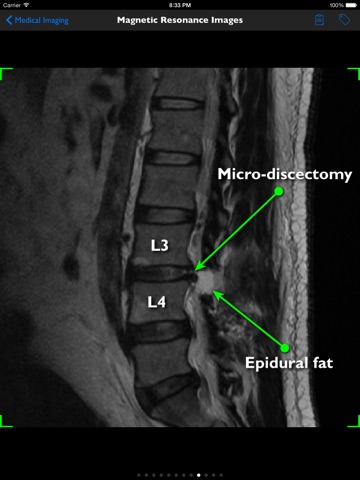

mLumbarMicroDiscectomy is an information resource for the surgical procedure known as a lumbar posterior discectomy. It presents surgical visualizations, medical images and educational notes for anyone seeking an introductory understanding of the procedure. FEATURES • Alternative Name – alternative name for a lumbar microdiscectomy • Disc Herniation - possible symptoms of a lumbar disc herniation • Cauda Equina Syndrome - the reasons for performing an urgent discectomy • Spontaneous Repair - spontaneous natural alleviation of a herniated disc’s symptoms • Nerve Compression - how a microdiscectomy is performed to remove pressure on the nerves and not to reduce back pain • Indications – the reasons for performing a lumbar microdiscectomy • Alternatives – alternative treatments to performing a lumbar microdiscectomy • Surgical Goals – clinical goals when performing a lumbar microdiscectomy • Surgical Technique – illustrates the surgical procedure • Medical Imaging - images of patients • No Smoking – the importance of not smoking before the procedure • Expectations – reasonable clinical expectations following a lumbar microdiscectomy • Rehabilitation – what is usually required following a lumbar microdiscectomy • Physical Therapy – importance of lifelong back care BENEFITS • detailed education • anatomically accurate • improved understanding, commitment, outcomes and satisfaction MORE INFORMATION mLumbarMicroDiscectomy is part of the lumbar spine library of patient education applications. Anatomate-apps have a range of spine apps including the reference apps iSpineCare, iSpineOperations and iSpinePainManagement.